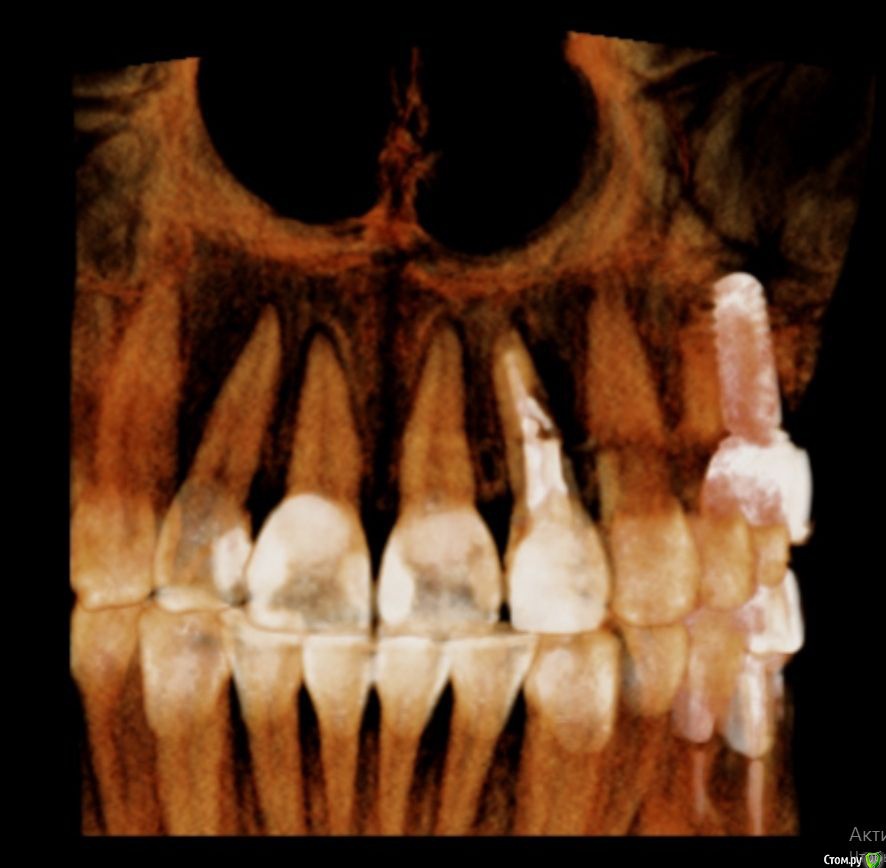

Lanasvlisa Опубликовано 21 апреля, 2017 Поделиться Опубликовано 21 апреля, 2017 Добрый вечер, уважаемые врачи! Вопрос по зубу 22, он леченый-перелеченный, сейчас на корне обнаружена киста, на десне над зубом свищевой ход. Какое ваше мнение: 1) удалять зуб и вместе с ним уйдет воспаление, прочищать все и заниматься имплантацией; или 2) можно каким-то образом удалить кисту, отсечь корень (читала о таком), но сам зуб не удалять? Если всё-таки 1), то можно ли осуществить в данном случае одномоментную имплантацию с нагрузкой? или можно одномоментную, но без нагрузки...? Спасибо огромное всем, кто посмотрит снимки и выразит свое экспертное мнение! С уважением, PS: прикрепляю скриншот из программы, но если этого недостаточно для определения диагноза и плана вмешательства, то скину ссылку на весь архив. Ссылка на комментарий

колесников Опубликовано 21 апреля, 2017 Поделиться Опубликовано 21 апреля, 2017 Резецировать там нечего,во время эндодонтического лечения произошла перфорация стенки корня зуба,вокруг этого участка очаг деструкции костной ткани. Это не лечится.По выставленной вами картинке объём деструкции не понятен. Решить возможность одномоментной имплантации и тем более немедленной нагрузки может только ваш лечащий доктор ,по результатам кт и в соответствии со своим опытом. Ссылка на комментарий

Lanasvlisa Опубликовано 22 апреля, 2017 Автор Поделиться Опубликовано 22 апреля, 2017 Здравствуйте, уважаемые врачи, и спасибо большое вам за оперативные ответы! Я не знаю, как найти срезы, полагаю, проекции - это то же самое, что и срезы? Я сделала их скриншоты+ еще три фото. А если я все-таки отправлю ссылку на весь архив, вы бы могли оценить объем разрушения костной ткани, чтобы предположить, насколько реально провести имплантацию в день удаления? У меня еще такие вопросы: если имплантацию удается провести сразу, то 1) через какой срок можно в моем случае заняться установкой коронки; 2) какая она должна быть; 3) если придется пользоваться "бабочкой" (я так понимаю, это единственный вариант, все временные коронки, в том числе клеевые, - это нагрузка, а каппа сюда тоже не подойдет?), то как потом происходит восстановление формы десны? Можно ли как-то сохранить десневые сосочки в случае отсроченной имплантации? Спасибо большое! Ссылка на комментарий